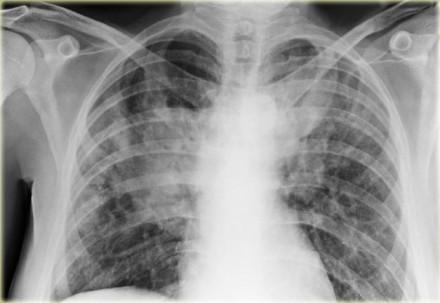

Seropositivity in patients with interstitial lung disease (ILD) without connective tissue disease (CTD) does not seem to contribute to improved outcomes or treatment response, a study has shown.

A prospective registry was used to identify a total of 1,570 non-CTD patients (with idiopathic pulmonary fibrosis, hypersensitivity pneumonitis, interstitial pneumonia with autoimmune features, or unclassified ILD) and 181 rheumatoid arthritis (RA)-ILD patients.